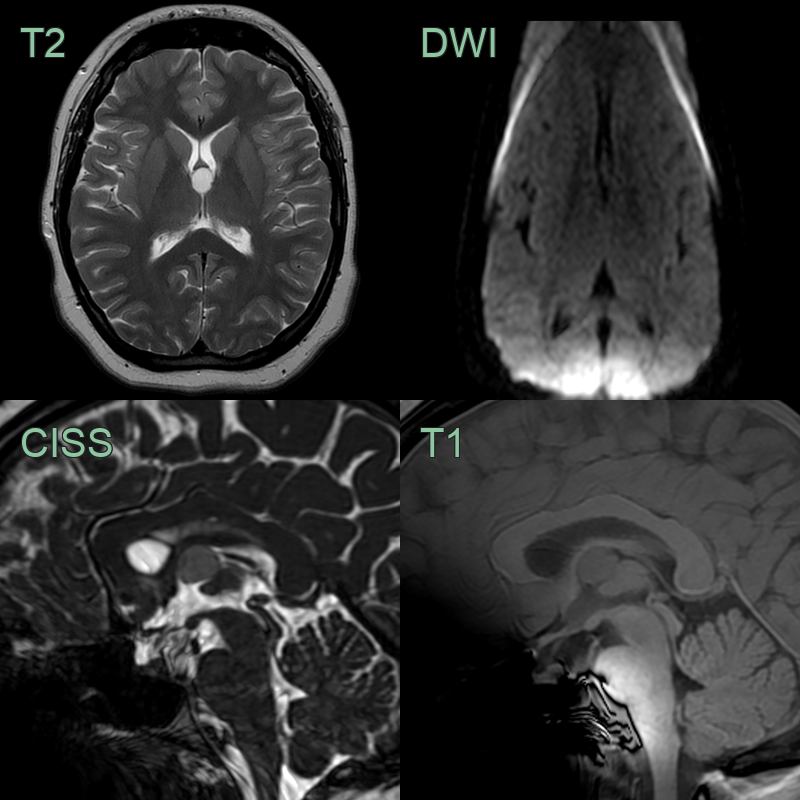

- MRI findings:

- T1-weighted: Variable signal intensity (hyperintense to CSF)

- T2-weighted: Usually hypointense to CSF

- FLAIR: Hyperintense signal

- Contrast enhancement: Typically minimal or absent

- DWI: No restricted diffusion

| Epidermoid cyst | Diffusion restriction on DWI, irregular margins |